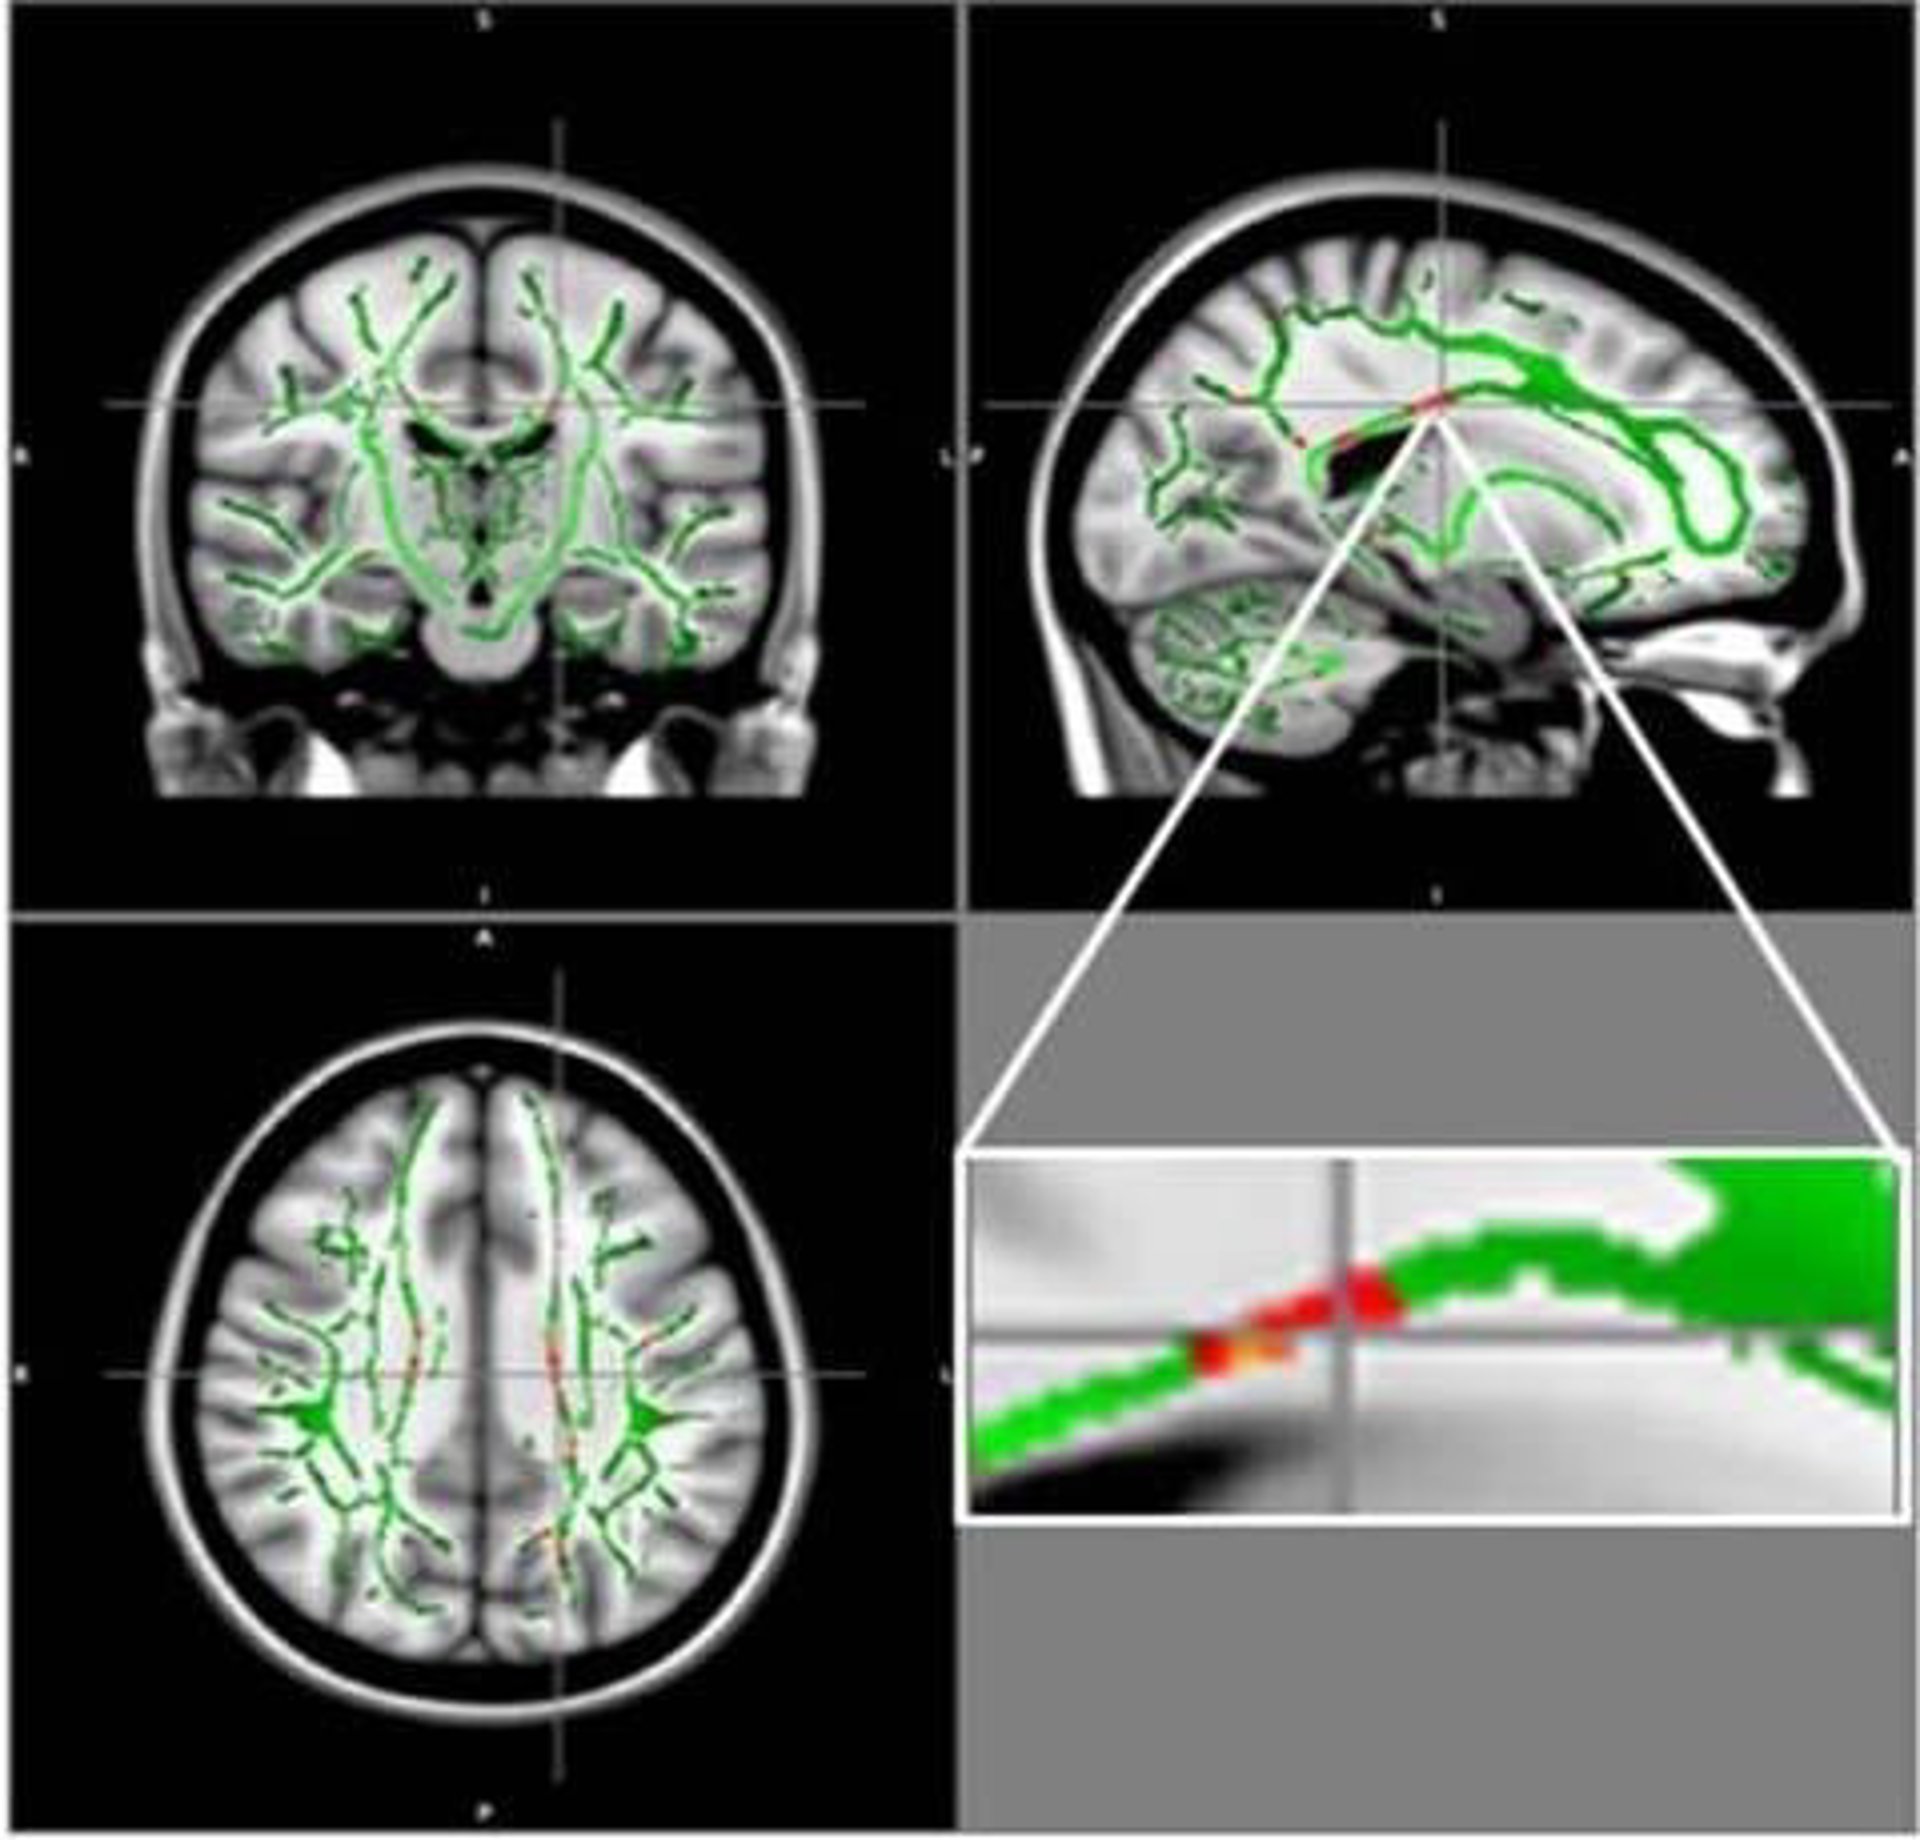

En rojo: Reducción de la AF en pacientes obesos en comparación con los controles, y esqueleto de FA (verde), superpuesto a la media de las imágenes de FA en la muestra.

Los investigadores compararon los resultados de la DTI de 59 adolescentes obesos y 61 adolescentes sanos de 12 a 16 años de edad. A partir del DTI, los investigadores derivaron una medida llamada anisotropía fraccional (AF), que se correlaciona con la condición de la materia blanca del cerebro. Una reducción del AF es indicativa de un aumento de los daños en la materia blanca.

Los resultados mostraron una reducción de los valores de AF en los adolescentes obesos en regiones localizadas en el cuerpo calloso, un conjunto de fibras nerviosas que conecta los hemisferios izquierdo y derecho del cerebro. También se encontró disminución de la AF en la corteza orbitofrontal, una región cerebral relacionada con el control emocional y el circuito de recompensa. En ninguna de las regiones cerebrales de los pacientes obesos había aumentado la AF.